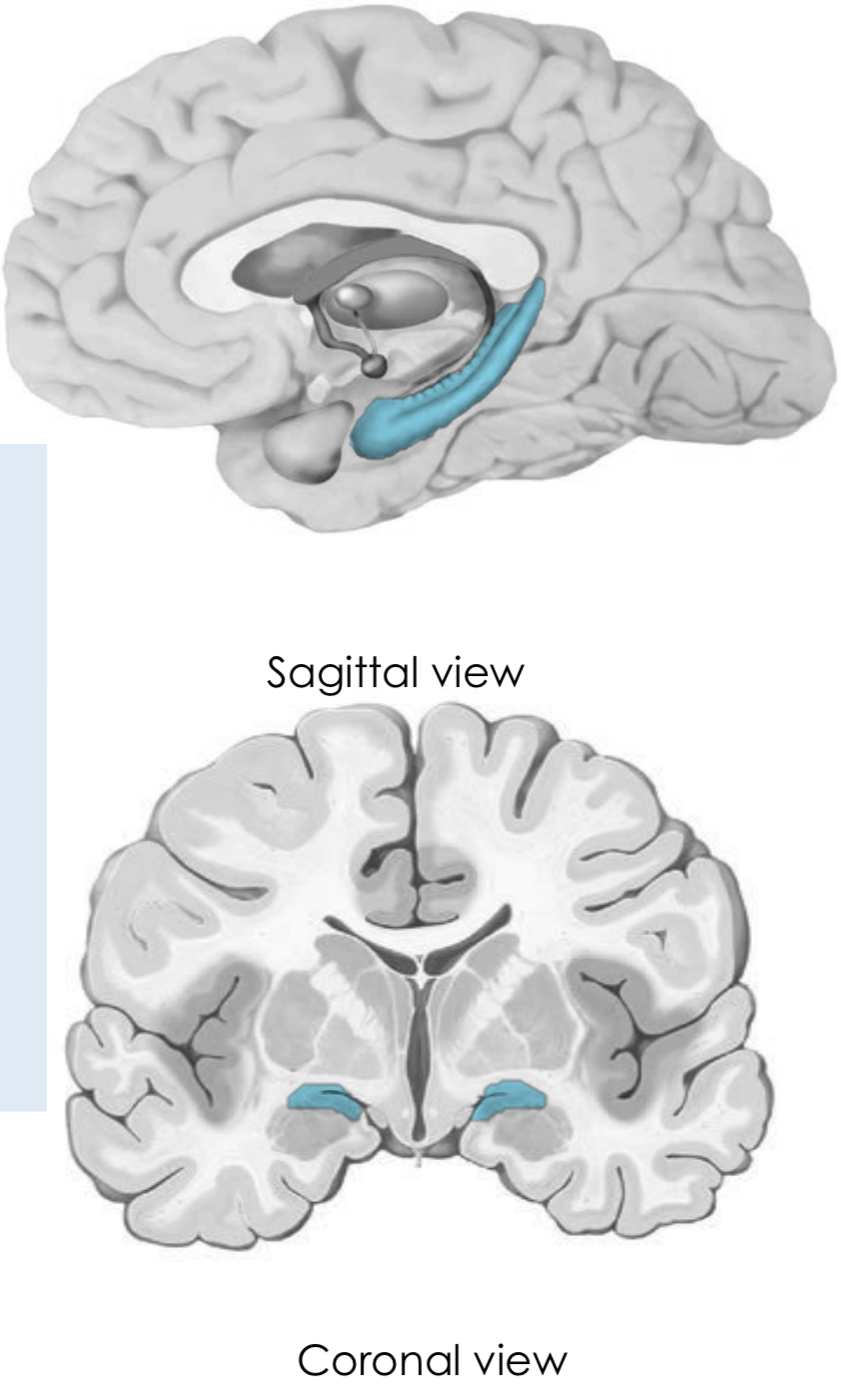

What is the hippocampal formation (hippocampus)?

Where is it found and what is its main role?

Nuclear complex (nerve cell bodies) in the medial temporal lobe

it is found deep to the parahippocampal gyrus

it is mainly involved in memory

What happens if there is a lesion in the hippocampal formation?

Lose the ability to form new memories

the hippocampal formation is mainly involved in formation of short term memories, so it is difficult for a single lesion to affect long term memories

Label the features of the hippocampal formation

What is their appearance like?

Dentate gyrus:

- strip of grey matter with a tooth-like appearance

Hippocampus proper:

- has a seahorse appearance in coronal section

the hippocampal formation forms the floor of the inferior horns of the lateral ventricles